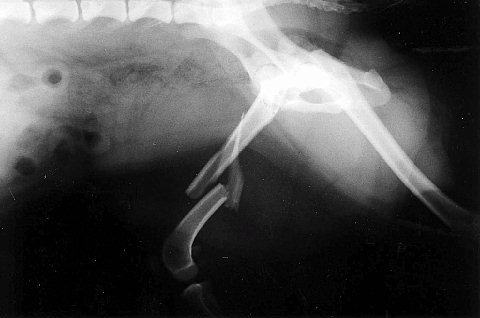

これは向かって右側の骨盤骨折と左側は仙腸関節離断と言います。この場合は仙腸関節を固定することで骨盤の骨折部分は元の位置に戻されて骨が癒合します。

手術から1年後の状態です。横にステンレスのピンをいれてます。本来は専用の長いボルトを使用しますが、この手術の時にはちょうどいいサイズのものがなくピンを代用したわけです。